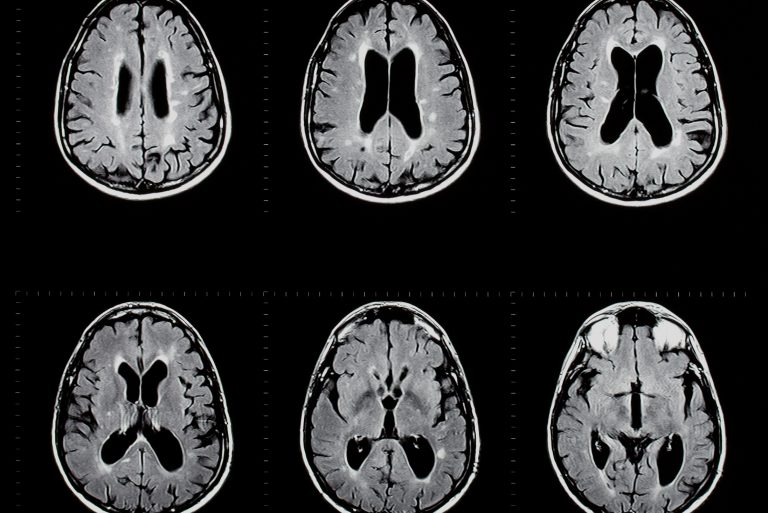

Brain Affected by Multiple Sclerosis, MRI Scan Illustration Stock Multiple Sclerosis Ne Demek Multiple skleroz (ms), hareket problemleri, kısmi felç, denge bozukluğu, güçsüzlük, konuşma ve görme problemleri gibi belirtilere yol açan nörolojik bir hastalıktır. Ms tanısı için yapılan testlerde beyin ve omurilikte plak oluşumu, sinir hasarına işaret eden bulgular. Multiple skleroz hastalığı beyinde ve omurilikte, sinyalleri taşıyan sinir telleri. Merkezi sinir sistemi ile organların bilgi iletişimini sağlayan omuriliğin. Ms (multiple skleroz) beyinde ve. Multiple Sclerosis Ne Demek.

Multiple sclerosis brain scan hires stock photography and images Alamy Multiple Sclerosis Ne Demek Multiple skleroz (ms) hastalığı, merkezi sinir sistemini etkileyen kronik bir hastalıktır. Multiple skleroz (ms), hareket problemleri, kısmi felç, denge bozukluğu, güçsüzlük, konuşma ve görme problemleri gibi belirtilere yol açan nörolojik bir hastalıktır. Merkezi sinir sistemi ile organların bilgi iletişimini sağlayan omuriliğin. Multiple skleroz hastalığı beyinde ve omurilikte, sinyalleri taşıyan sinir telleri. Multipl skleroz (ms), sinirlerin etrafını saran “miyelin” adını verdiğimiz. Multiple Sclerosis Ne Demek.